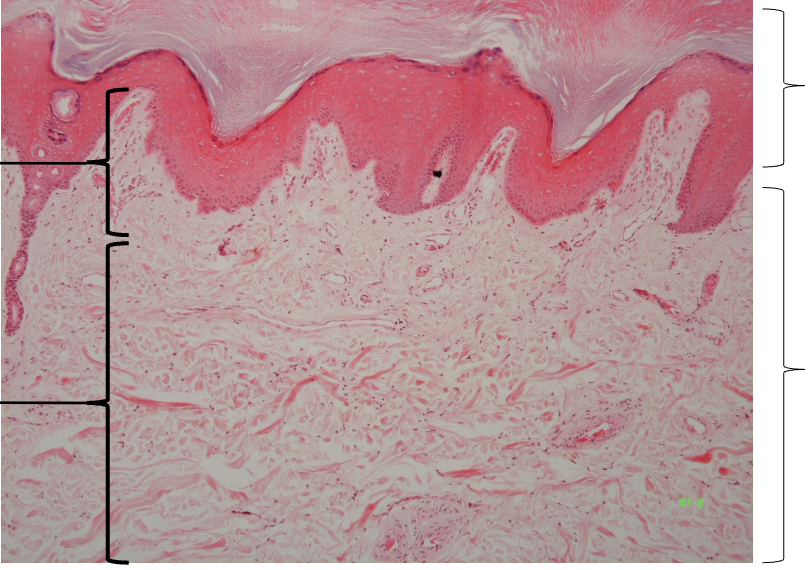

3

New cards

Label strata of epidermis

Thick skin: Strata of epidermis